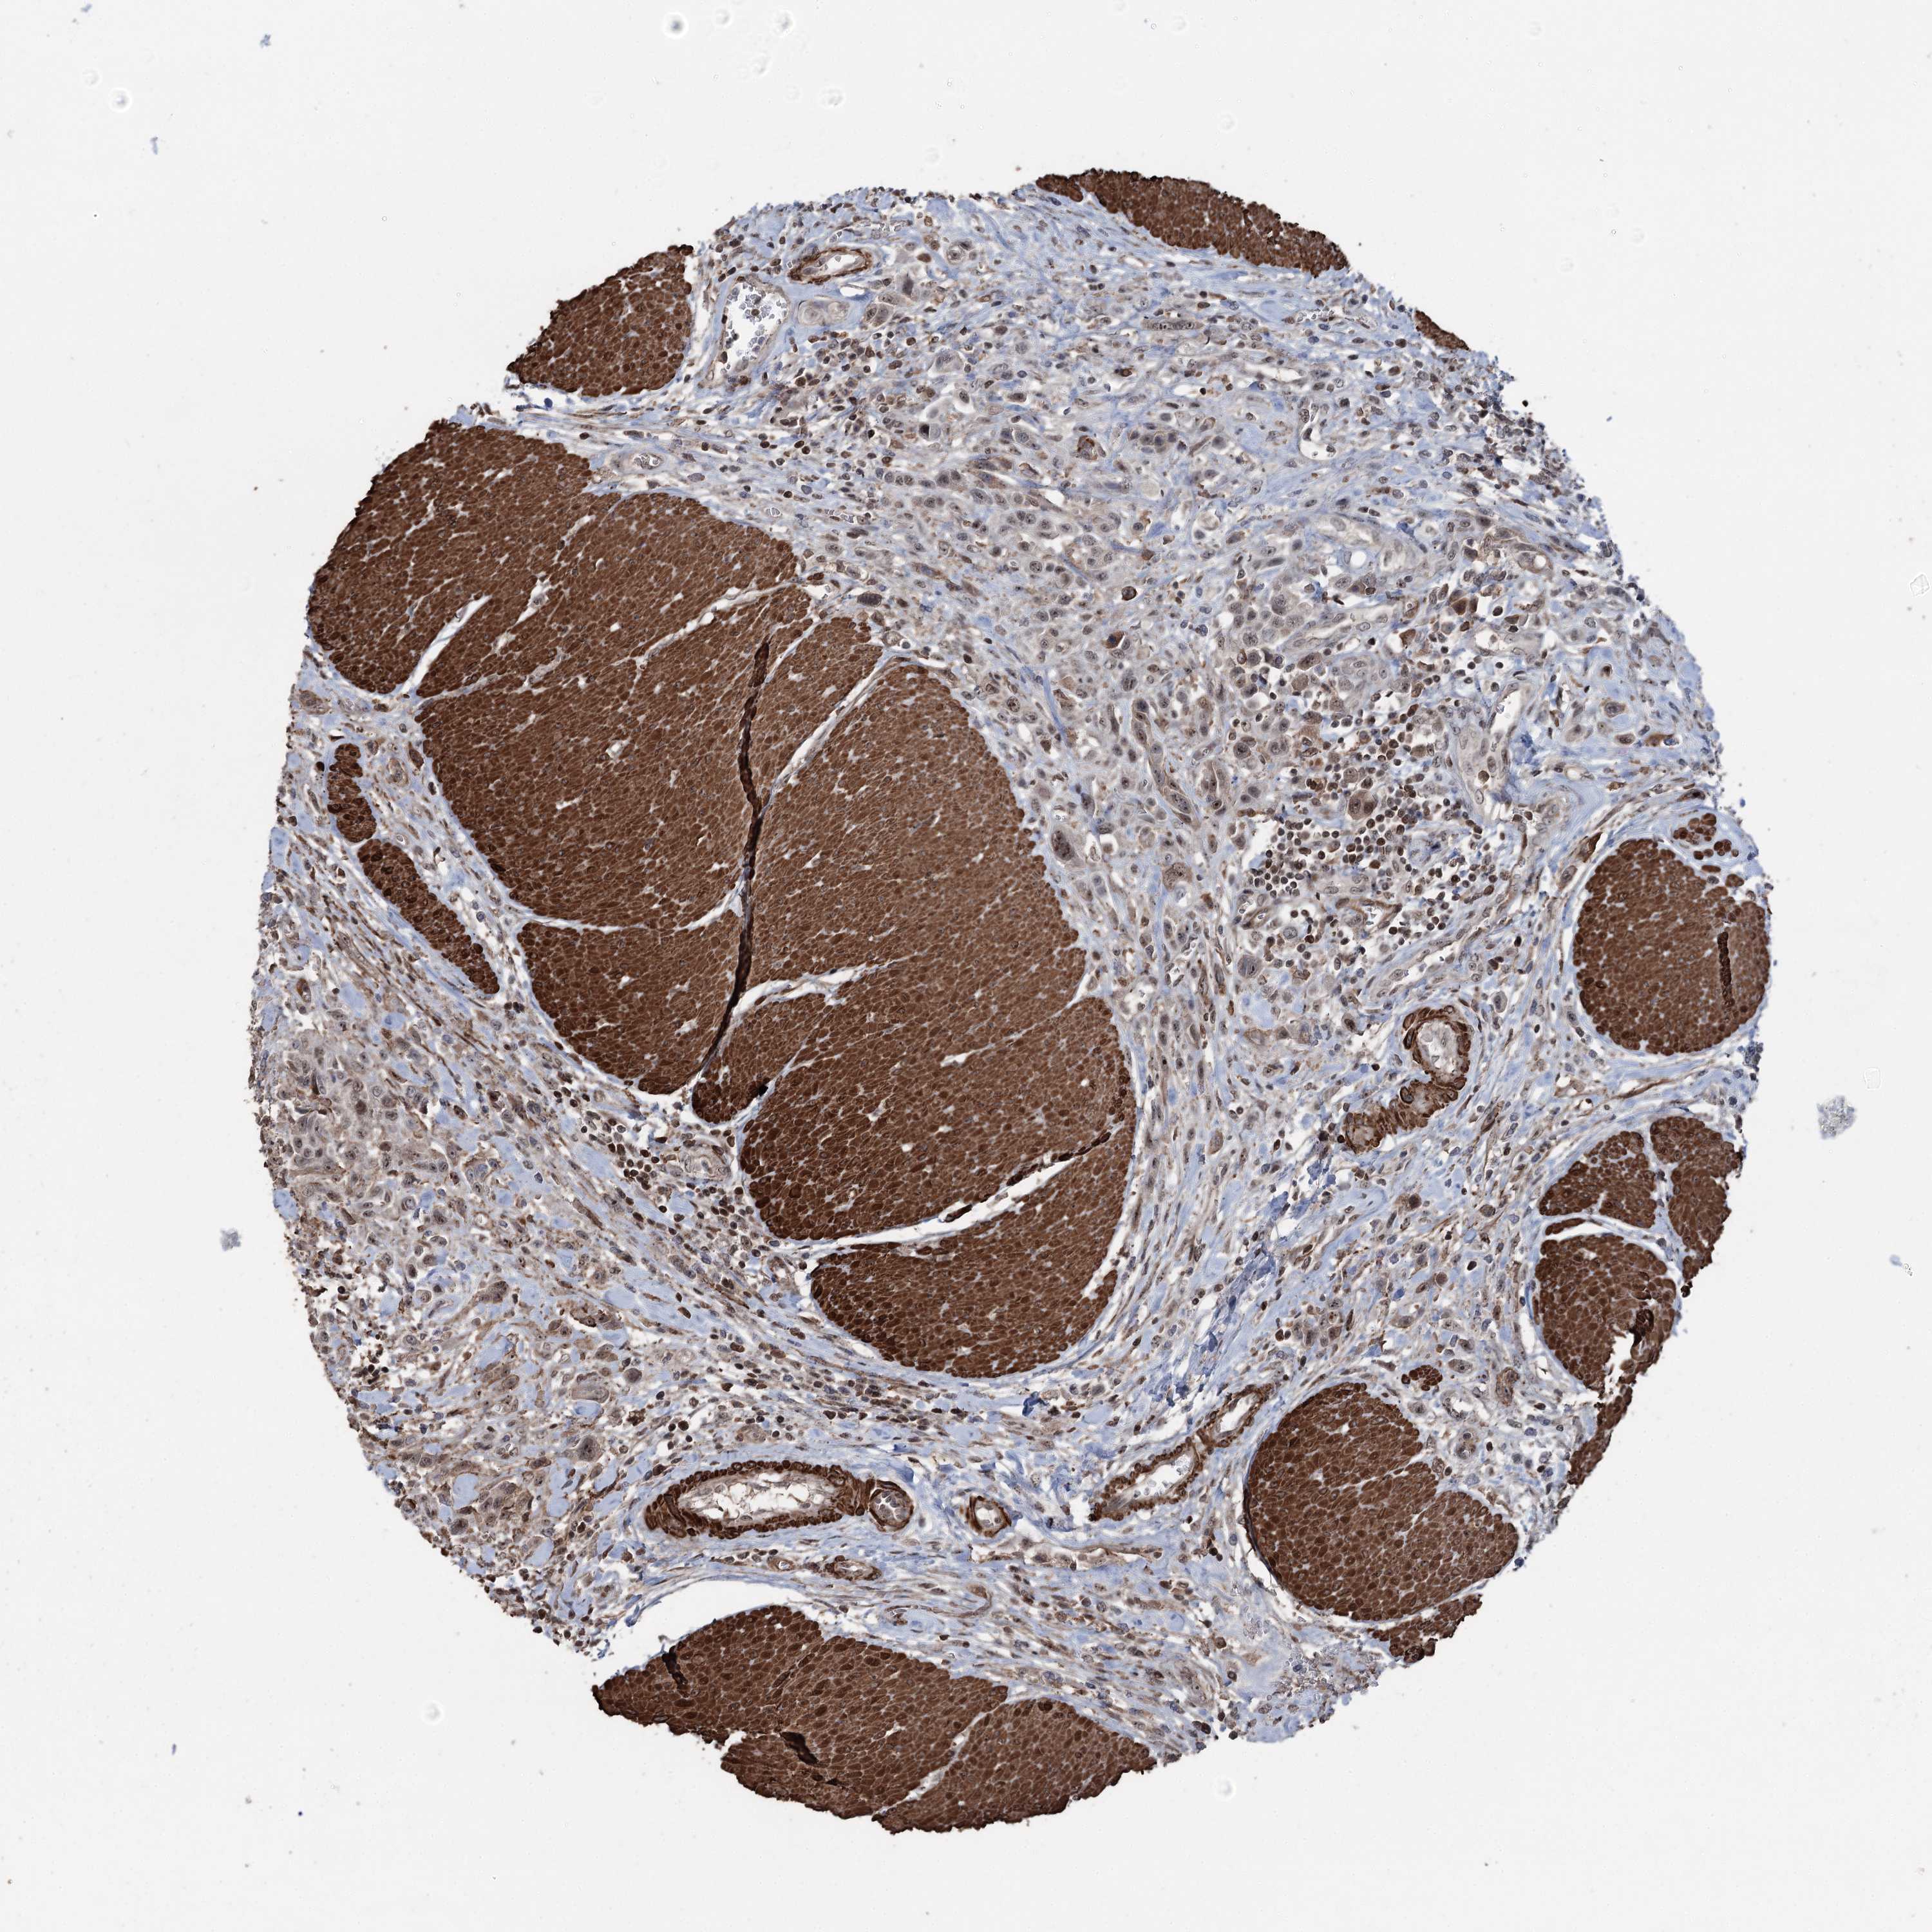

UROTHELIAL CANCER - Protein expressioni

A mouse-over function shows sample information and annotation data. Click on an image to view it in a full screen mode. Samples can be filtered based on level of antibody staining by selecting one or several of the following categories: high, medium, low and not detected. The assay and annotation is described here.

Antibody stainingi

Antibody staining in the annotated cell types in the current human tissue is reported as not detected, low, medium, or high, based on conventional immunohistochemistry profiling in selected tissues. This score is based on the combination of the staining intensity and fraction of stained cells.

Each image is clickable and will lead to virtual microscopy that enables deeper exploration of all samples and also displays staining intensity scores, fraction scores and subcellular localization as well as patient and tissue information for each sample.

Antibody HPA038704

Staining

High

Medium

Low

Not detected

Intensity

Strong

Moderate

Weak

Negative

Quantity

>75%

75%-25%

<25%

None

Location

Nuclear

Cytoplasmic/membranous

Cytoplasmic/membranous,nuclear

Urothelial carcinoma, High grade

Urothelial carcinoma, Low grade